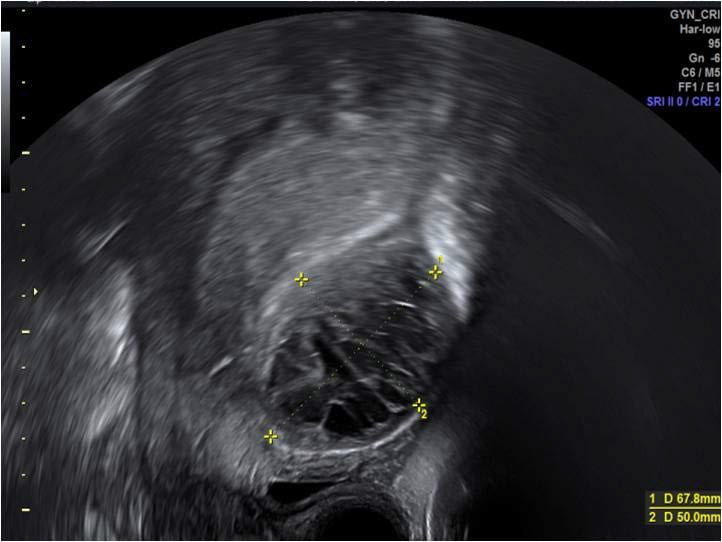

Figure 11: Post caesarean section haematoma originating from the anterior uterine wall, posterior to the urinary bladder,seen in the sagittal plane on transvaginal scan 7 days post procedure.

figure 11